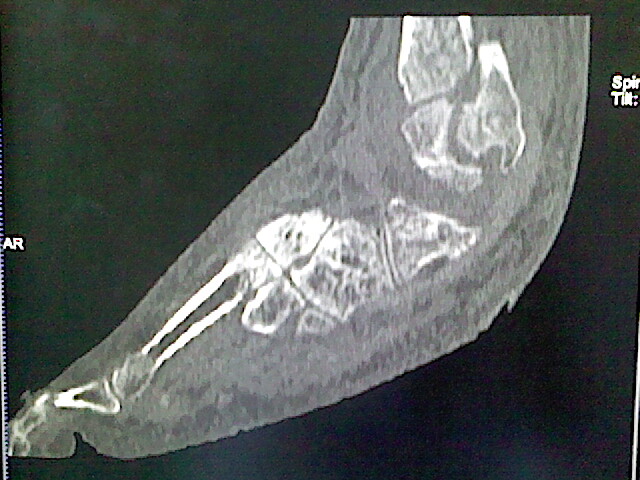

男,76岁,左小腿疼痛,不能站立

本例骨质改变主要表现为滑膜或韧带区的骨侵蚀融解(胫腓联合区骨质破坏无硬化边),距骨后部骨质破坏区有硬化边及死骨样改变.所以,本例考虑关节结核可能性大,绒毛膜结节性滑膜炎多发于中年,且极少见于膝髋以外的关节,骨质硬坏也以压陷吸收为主,有明显的硬化边,骨膜增生呈结节状(可以mr鉴别),所以本例暂除外.

另不除外可引起相似表现的其他炎症如布氏杆菌性关节炎等